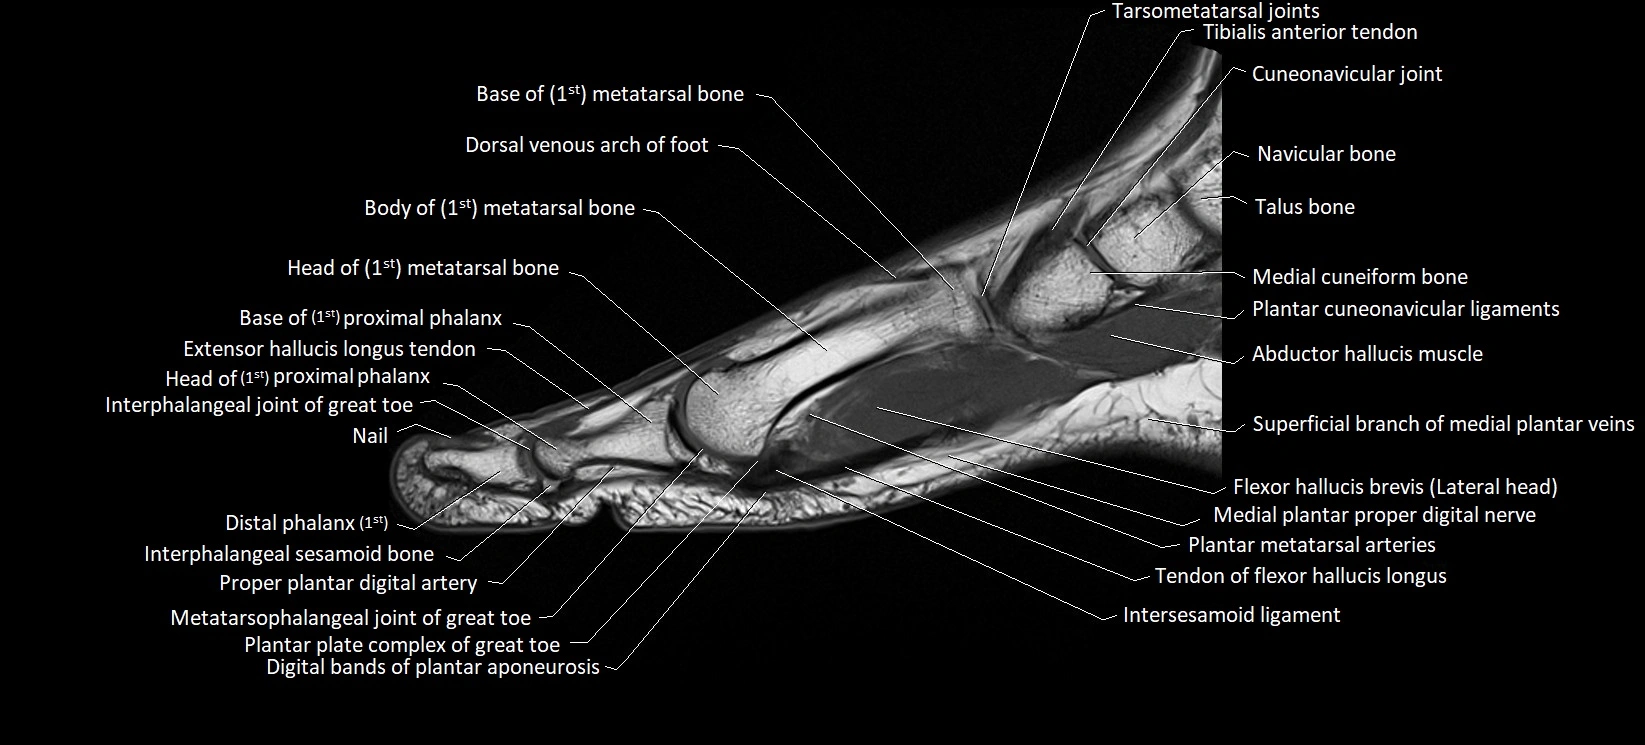

MRI image